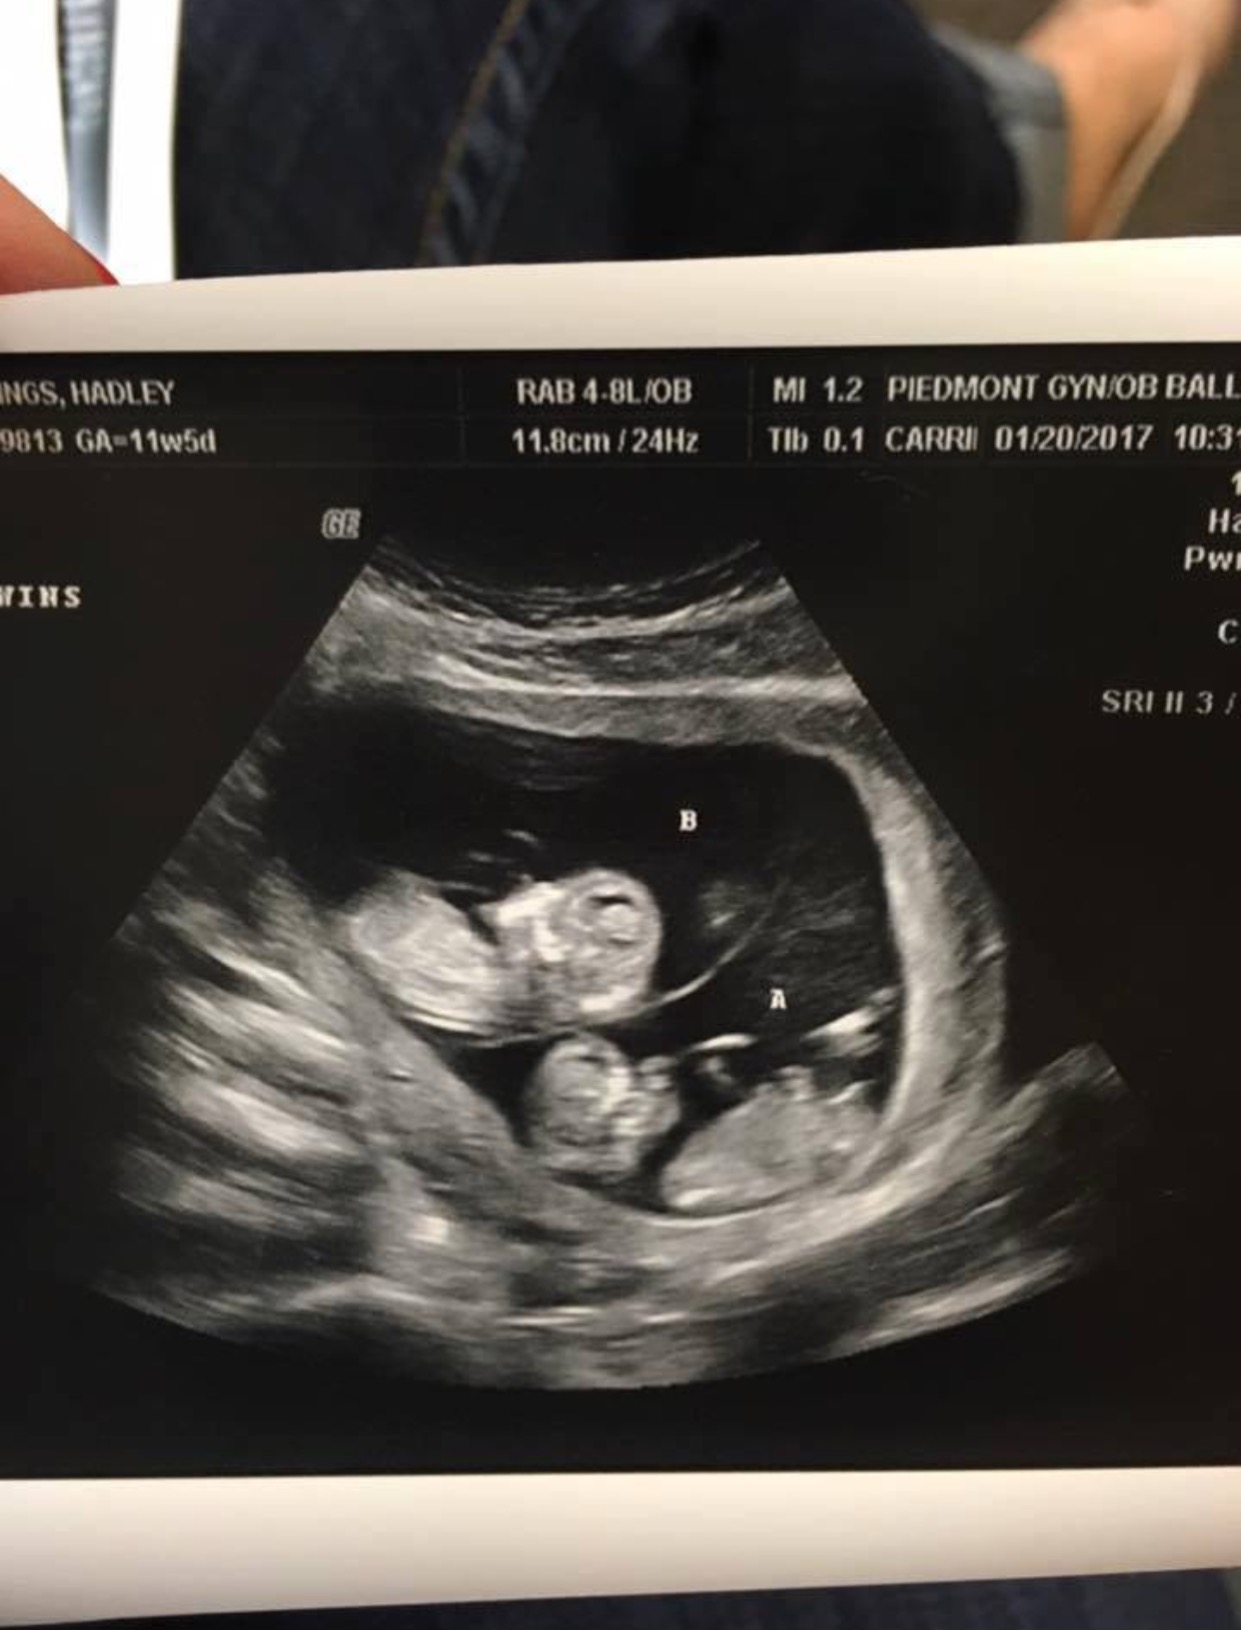

A través de la cuenta de Facebook que abrieron, la familia anunció el embarazo hace unos meses con una imagen del ultrasonido.

¡Todos ustedes nos han sostenido con sus oraciones y estamos muy agradecidos! ¡Ahora le pedimos que agreguen dos Eddings más a sus oraciones! Estamos esperando gemelos este verano!”